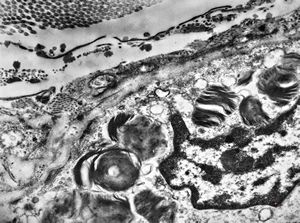

F, 25y. | metachromatic leukodystrophy … n. suralis